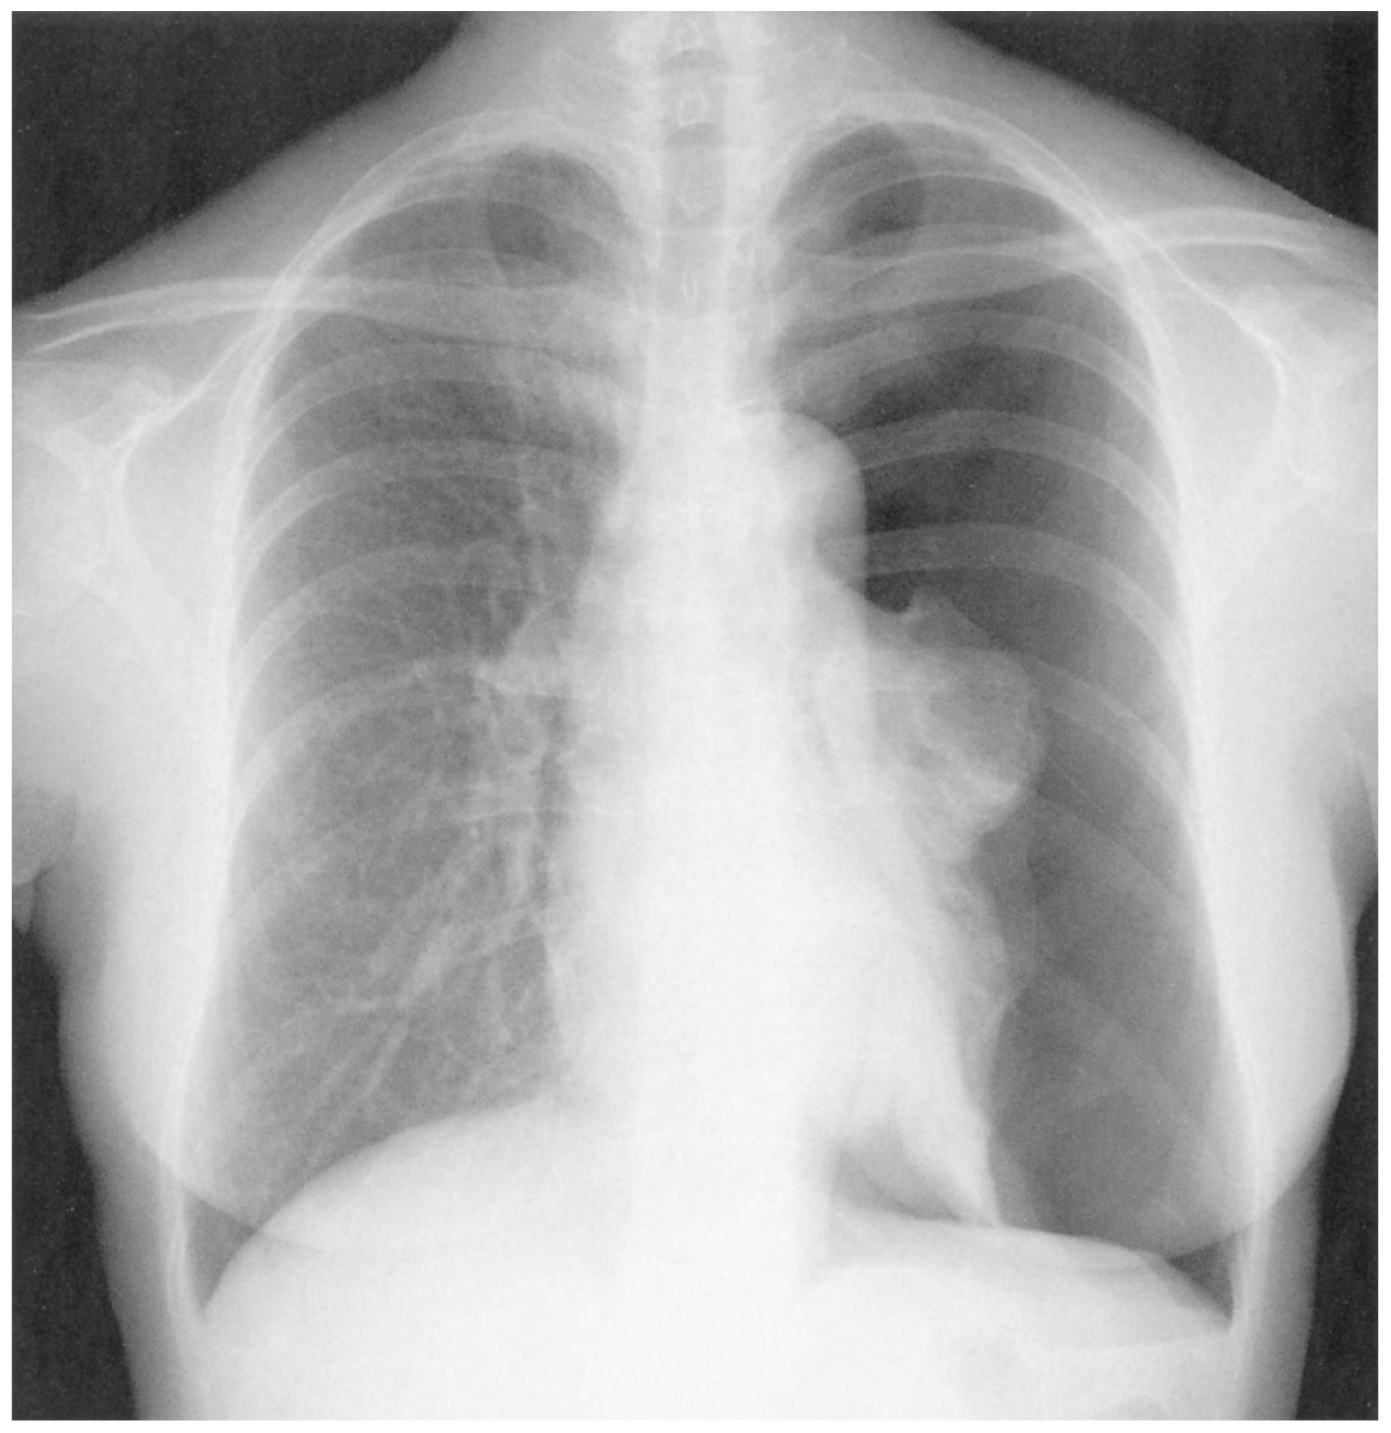

40歳の女性。突然の胸痛と呼吸困難を主訴に救急車で搬入された。意識レベルはJCSⅡ-10。身長168cm,体重60kg。体温36.9℃。心拍数120/分,整。血圧80/60mmHg。呼吸数30/分。SpO2 91%(リザーバー付マスク10L/分 酸素投与下)。毛細血管再充満時間3秒。皮膚はチアノーゼを認める。眼瞼結膜に貧血を認めない。頸静脈の怒張を認める。呼吸音は左前胸部で消失し,打診で左胸部に鼓音を認める。胸部エックス線写真を下に示す。

無料会員登録していただくと、実際の解説をすべて見ることができます。急性の呼吸困難を主訴とする疾患としては,喉頭浮腫,気道異物,自然気胸,気管支喘息,慢性閉塞性肺疾患の急性増悪などの呼吸器疾患,心不全(急性,慢性の急性増悪),肺血栓塞栓症などの循環器疾患が代表的である。この症例では呼吸器感染症と心不全が疑われるが,胸部エックス線写真は肺炎像というよりも両心不全を示唆する所見を示している。診断:心不全(両心不全)(Nohria分類wet and warm) 選択肢考察 ×a 強い呼吸困難,胸痛などにより安静が保てない場合には,血管拡張による前負荷軽減と,交感神経抑制による心筋酸素消費量の減少を目的としてモルヒネを使用する。この症例ではモルヒネが必要となるほどの興奮状態ではない。